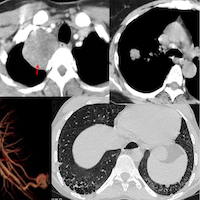

56-years old with an incidentally detected lung nodule in the superior segment of the right lower lobe of the lung. It showed one calcific speck. No contrast. No PET. There was extrapleural fat retraction, suggesting this could be extra-pulmonary.

On biopsy, it was firm. Histopath shows cartilage.

This is a peripheral chondroid hamartoma of the lung. Likely so longstanding, that the pleura has puckered around it.